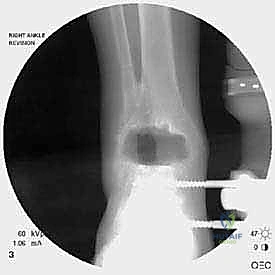

التشخيص الدقيق: حجر الأساس لنجاح العملية

- الأشعة السينية مع تحميل الوزن (Weight-bearing X-rays): لتقييم الزوايا الميكانيكية وتحديد مدى هبوط المفصل أو وجود كسور في الكعب.

كسور الكعبين (Malleolar Fractures) المصاحبة للمفصل الصناعي

من أعقد التحديات التي تواجه جراحي العظام هي حدوث كسور في الكعب الداخلي (Medial Malleolus) أو الخارجي (Lateral Malleolus) في وجود مفصل صناعي. تحدث هذه الكسور لعدة أسباب:

علاج هذه الكسور يتطلب مهارة فائقة من الدكتور محمد هطيف، حيث يتم استخدام تقنيات الجراحة الميكروسكوبية وتثبيت الكسور باستخدام صفائح معدنية دقيقة ومسامير (Locking Plates) دون المساس بثبات المفصل الصناعي، أو يتم دمج علاج الكسر ضمن عملية مراجعة المفصل الكلية إذا كان المفصل نفسه تالفاً.